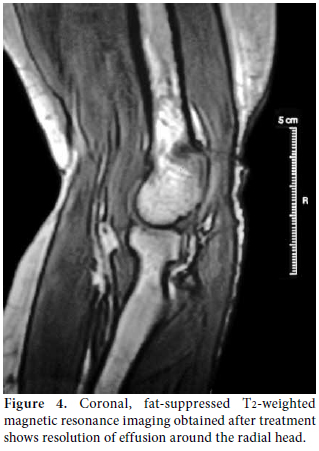

Plain radiography of the left elbow, musculoskeletal ultrasonography (US), and magnetic resonance imaging (MRI) were used to make a visual representation of the pathology. The plain radiography showed soft tissue swelling with a normal articular surface. The US assessment (7.5 MHz linear transducer, gray scale, General Electric Medical Systems, Milwaukee, Wisconsin, USA) pointed out an “eye-shaped”, demarcated, hypoechoic bulging mass with regard to articular effusion that was in close contact with the “contoured eyebrow-shaped” fascicular PIN. It had swelled to 2 mm compared with 1 mm on the asymptomatic right side (Figure 2). The MRI indicated hyperintense, demarcated fluid around the radial head, neck, and distal humerus (Figure 3).

The diagnostic approach, including a careful clinical examination, non-invasive imaging techniques (US, MRI), and electrophysiological assessment were sufficient to obtain the diagnosis of PIN palsy. The patient refused to be assessed surgically, so we reconsidered and rearranged her medication by increasing the methotrexate dosage to 15 mg/week and also subcutaneously, drained the fluid and injected methylprednisolone acetate (40 mg/mL) intra-articularly by using the lateral approach to the center of the triangle formed by the lateral olecranon, the head of the radius, and the lateral epicondyle.[7] The patient was followed up via clinical, US and electrophysiological assessments every three months. Her symptoms improved the second month after the injection, and they completely resolved at the sixth month without surgical intervention. The ultrasonographic resolution was noted at the third month, but better recruitment was obtained at sixth month from the affected muscles. However, fibrillation potentials remained albeit with a smaller amplitude size. Revisualization by MRI, repeated at the 18th month, detected resolved effusion with clinical stability (Figure 4).